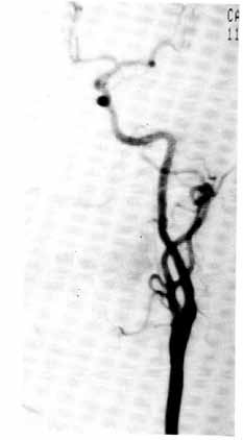

Uredna kontrolna postoperativna arteriografija

karotidnih arterija nakon everzione endarterektomije.